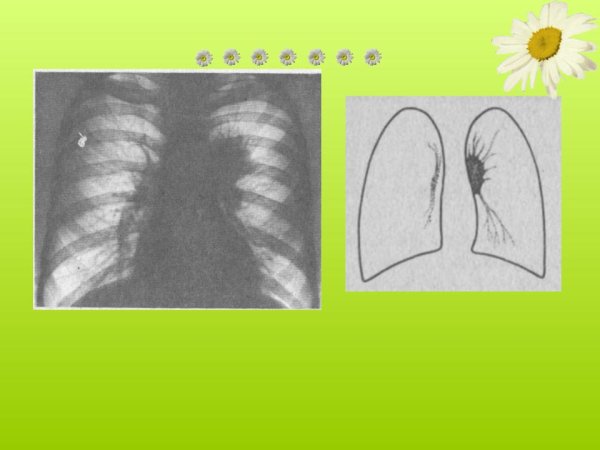

Патология легочного рисунка - это состояние, при котором обнаруживается изменение образца распределения сосудистых и бронхиальных структур в легких. Это может быть вызвано различными причинами, такими как хронические заболевания легких, врожденные аномалии или инфекционные процессы. При патологии легочного рисунка могут наблюдаться различные изменения на рентгенограммах, такие как утолщение сосудов, усиление бронхиального образца или появление тени. Диагностика и лечение этого состояния требуют комплексного подхода, основанного на клинических данных и дополнительных исследованиях. Целью такого лечения является устранение основной причины патологии легочного рисунка и восстановление нормальной структуры и функции легких.

Синдром деформации легочного рисунка